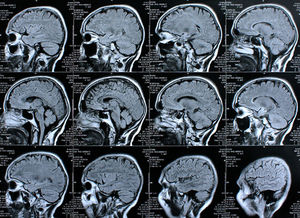

Sie sind hier: Startseite Nachrichten Gesundheit Wissenschaftler lassen Gedanken sprechen Scan: Computer kann Gedanken lesen.

Scan: Computer kann Gedanken lesen.